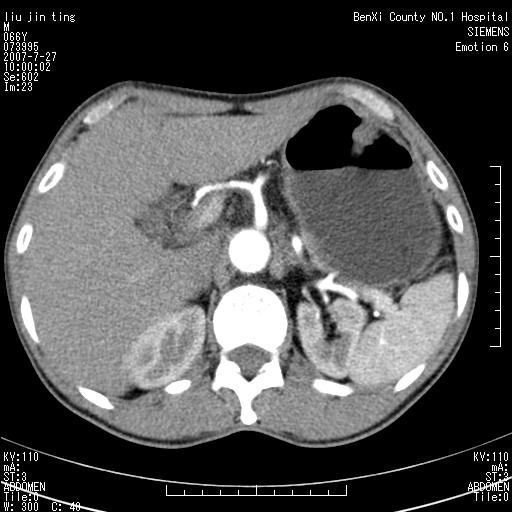

腹痛,背痛,无恶心呕吐,不黄,彩超示胰腺钩癌,ct扫描病灶平扫30-40hu,增强后动脉期40--60hu,静脉期50-68hu,真的是钩突上的么?您要试一试么?

动脉期

静脉期

沿着肠系膜上动脉呈匍匐性生长的软组织肿块,形态不规则,包绕肠系膜上动脉,呈明显强化,考虑来源于肠系膜的恶性肿瘤

沿着肠系膜上动脉呈匍匐性生长的软组织肿块,形态不规则,包绕肠系膜上动脉,呈轻-中度强化,考虑来源于肠系膜的恶性肿瘤。

钩突是正常的,只见腹膜后淋巴结的肿大,考虑淋巴瘤或转移可能。

支持!恶性纤维组织细胞瘤可能,与淋巴瘤及淋巴结转移鉴别(腹主动脉周围清晰,其他部位亦未见明显肿大淋巴结)。